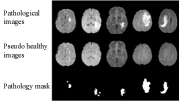

Refer to caption

(a) Example results

(b) Simple illustration of our method

Figure 1: Example results and simple illustration of our method. The three rows of (a) show input pathological images, corresponding pseudo healthy images, and pathology segmentation masks, respectively. Images are taken from the BraTS dataset. In (b) a pseudo healthy image x~hsubscript~𝑥\tilde{x}_{h} and a pathology mask m~psubscript~𝑚𝑝\tilde{m}_{p} are generated from a pathological image xpsubscript𝑥𝑝x_{p}, and then finally a reconstructed image x^psubscript^𝑥𝑝\hat{x}_{p} is generated from x~hsubscript~𝑥\tilde{x}_{h} and m~psubscript~𝑚𝑝\tilde{m}_{p}.